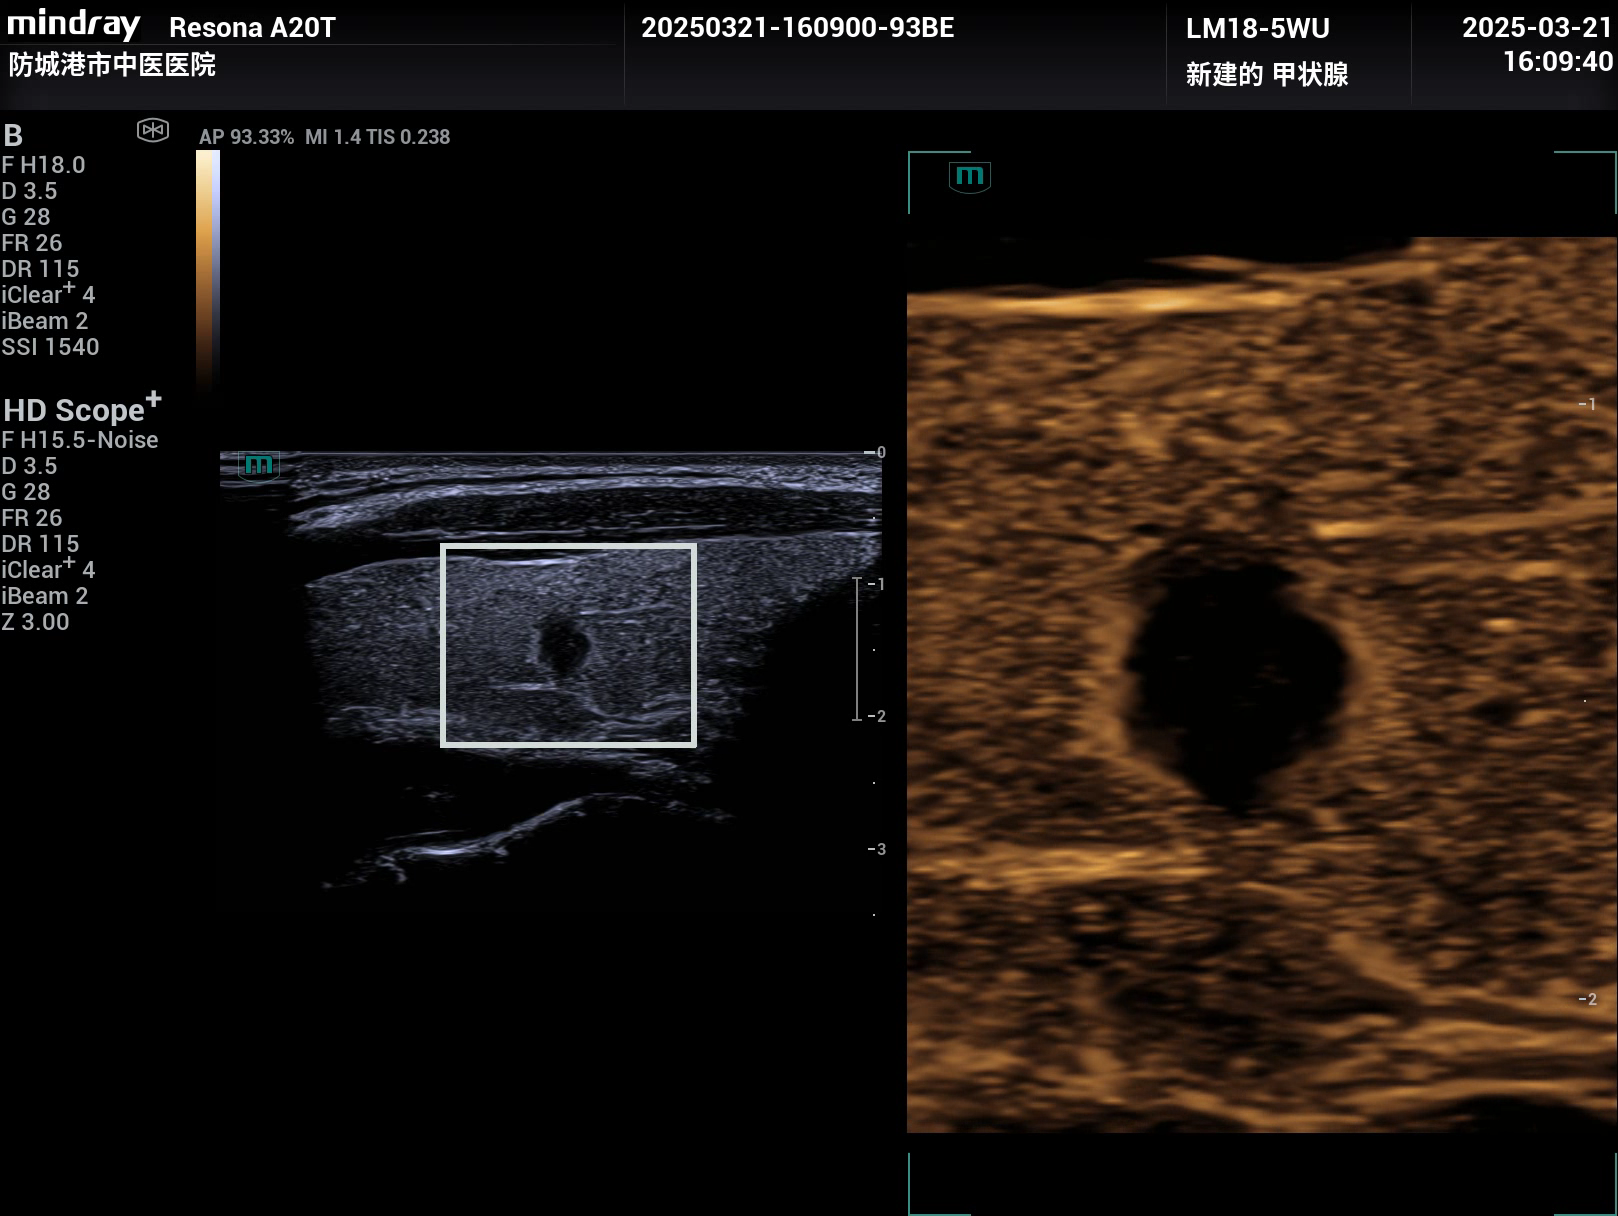

病例,甲状腺癌,超微血流,睿瞳技术,超声造影,防城港市中医院超声科,迈瑞Resona A20,2025年3月